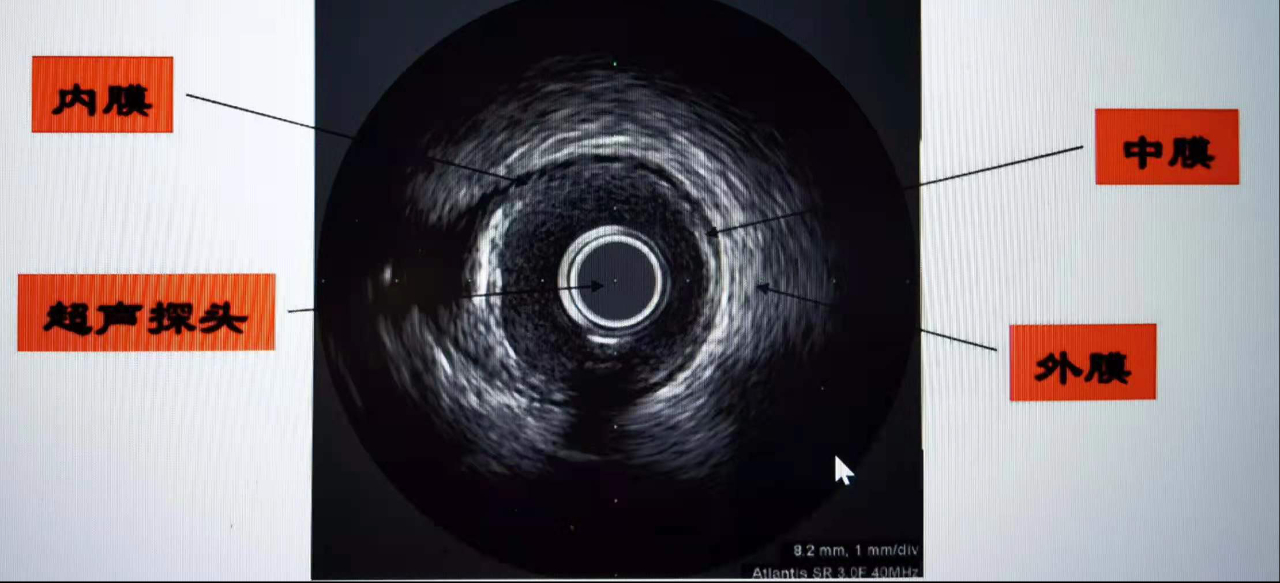

眾所周知,心臟、腹部可以做超聲檢查,血管內超聲(Intra Vascular UltraSound,IVUS)技術。簡單通俗地說,就是在心臟血管內做超聲檢查,將微型化的超聲探頭通過導管的技術送入血管腔內,從而提供管壁在內的橫截面圖像。精細程度堪稱心血管介入術中醫生的“火眼金睛”。

目前確診冠心病的主要手段是冠脈造影,但該技術只能對血管內血流情況進行成像,且容易受造影角度的影響,不能顯示病變所在的管壁和粥樣斑塊,不能提供粥樣斑塊的形態和性質。IVUS利用安裝在心導管頂端的微型超聲探頭,實時顯示血管的截面圖像,能清晰顯示管壁結構的厚度、管腔大小和形狀等,精確地測量血管腔徑及截面積,甚至可以辨認鈣化、纖維化和脂質池等病變,發現冠脈造影不能顯示的血管早期病變,在支架植入前為選擇合適的支架提供準確的參考依據,使術者能夠更好地選擇支架的直徑和長度,使支架和血管更好地匹配。在支架植入后,可對支架的大小、位置、形狀、貼壁程度、對稱性和展開滿意度進行系統的評價,保證支架充分而不過度擴張。